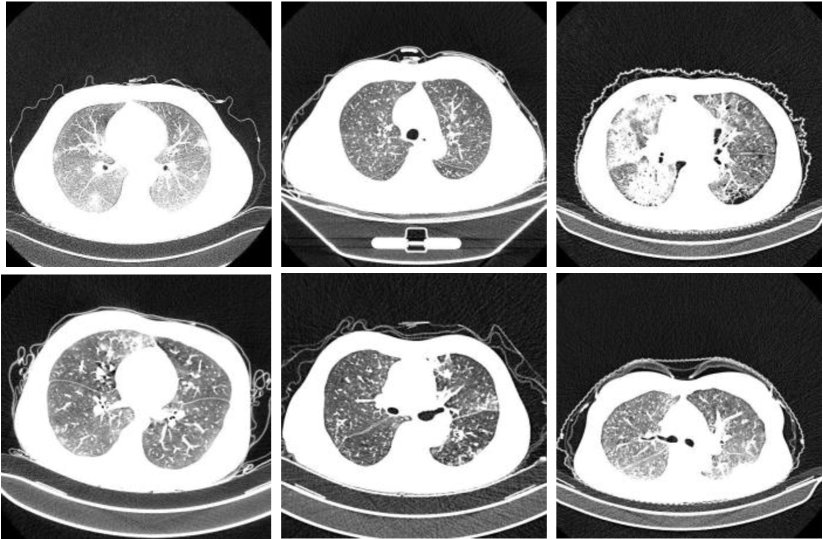

In the past, Artificial intelligence (AI) has gained a reputable position in the field of clinical medicine. And in such chaotic situations, AI can help the medical practitioners to validate the disease detection process, hence increasing the reliability of the diagnosis methods and save precious human lives. Currently, the biggest challenge faced by AI-based methods is the availability of relevant data. AI cannot progress without the availability of abundant and relevant data. In this paper, we collected the data CT scan data for 34006 slices from the 3 different hospitals. The data is scanned by 6 different scanners shown in Table II. In addition, we collected the third party dataset [29, 30] from different sources to validate the federated learning methods. Moreover, the collected dataset is publicly available via GitHub (https://github.com/abdkhanstd/ COVID-19). The collected data set contains the Computed Tomography scan (CT) slices for 89 subjects. Out of these 89 subjects, 68 were confirmed patients (positive cases) of the COVID-19 virus, and the rest 21 were found to be negative cases. The proposed dataset CC-19 contains 34,006 CT scan slices (images) belonging to 89 subjects out of which 28,395 CT scan slices belong to positive COVID-19 patients. Figure 6 shows some 2D slices taken from CT scans of the CC-19 dataset. Moreover, some selected 3D samples from the dataset are shown in Figure 7. The Hounsfield unit (HU) is the measurement of CT scans radiodensity as shown in Table III. Usually, CT scanning devices are carefully calibrated to measure the HU units. This unit can be employed to extract the relevant information in CT Scan slices. The CT scan slices have cylindrical scanning bounds. For unknown reasons, the pixel information that lies outside this cylindrical bound was automatically discarded by the CT scanner system. But fortunately, this discarding of outer pixels eliminates some steps for preprocessing.

Refer to caption

Figure 6: Some random samples of CT scan 2D slices taken from CC-19 dataset.